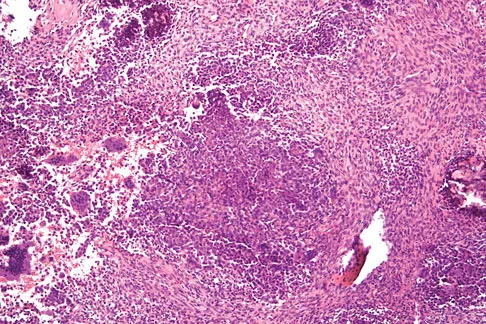

Question 17High Yield

Figures 12a through 12e show the radiograph, MRI scans, and biopsy specimens of a 17-year-old boy. What is the most likely diagnosis?

Explanation

The images show an epiphyseal lesion. The MRI scan shows extensive bone edema surrounding the lesion, consistent with chondroblastoma. Histology shows polygonal chondroblasts in a cobblestone-like pattern and areas of calcification consistent with chondroblastoma. Although some giant cells are seen, the age of the patient and the polygonal chondroblasts differentiate this lesion from giant cell tumor. Clear cell chondrosarcoma is an epiphyseal lesion that occurs in an older population, and the cells have clear cytoplasm. This lesion is not producing bone on imaging or histologic specimen, eliminating osteosarcoma. Tuberculous septic arthritis can be an epiphyseal lesion, but granulomas would be seen on histology. Menendez LR (ed): Orthopaedic Knowledge Update: Musculoskeletal Tumors. Rosemont, IL, American Academy of Orthopaedic Surgeons, 2002, pp 103-111.